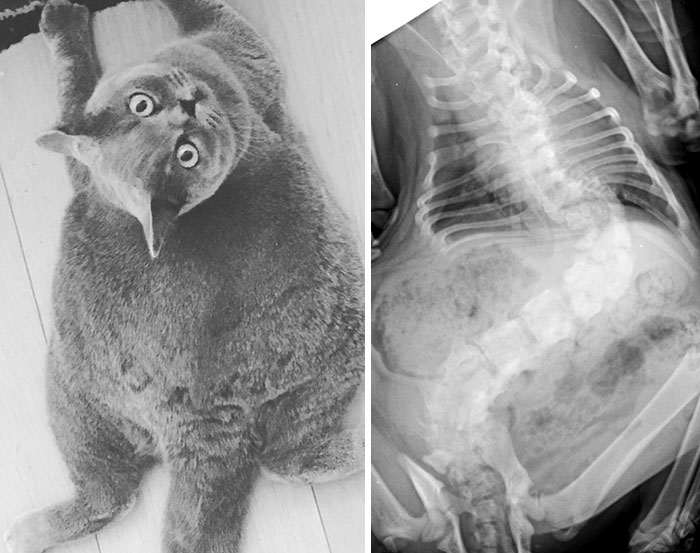

Рентген беременной кошки

Рентген кошки со сколиозом, из-за которого она круглая